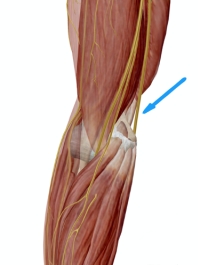

Εικ 1. Ο Αχίλειος τένοντας καταφύεται στο οπίσθιο τμήμα της πτέρνης

Εικόνα.1. Ο αχίλλειος τένοντας κατφύεται στο οπίσθιο τμήμα της πτέρνας. Η ρήξη συνήθως είναι στο κάτω τριτημόριο αυτού.